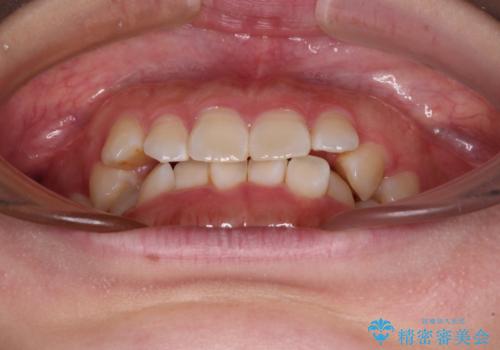

前歯のデコボコを整える インビザラインによる矯正治療

- 上下前歯のデコボコを気にして来院された患者様です。

叢生は軽度であり、ワイヤー矯正でもマウスピース矯正でも対応可能であったので、好きな装置を選んでもらいました。

相談の結果、インビザラインによる矯正治療を行うこととしました。